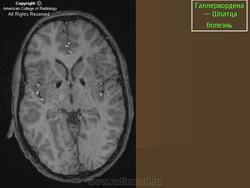

Галлервордена - Шпатца болезнь (J. Hallervorden, 1882-1965, нем. невропатолог; H. Spatz, совр. нем. невропатолог; син. ригидность прогрессирующая) - наследственная болезнь, связанная с нарушением обмена железа и липидов, проявляющаяся в возрасте 7-9 лет повышением мышечного тонуса, гиперкинезами, прогрессирующей деменцией, снижением зрения и пигментным ретинитом; наследуется по аутосомно-рецессивному типу.

Болезнь Галлервордена - Шпатца - наследственное заболевание экстрапирамидной системы, связанная с нарушением обмена железа и липидов и повреждением бледного шара и черной субстанции. Тип наследования аутосомно-рецессивный. При патоморфологическом исследовании характерным признаком является гиперпигментация бледного шара и черной субстанции. Обнаруживается пигментация коры полушарий большого мозга и таламуса. Пигмент находится внутри невронов и глиальных клеток, расположенных около сосудов; содержит железо (вместе с тем каких-либо нарушений обмена железа в организме не обнаружено). Наблюдаются утолщение и фрагментация аксонцилиндров в пораженных областях. Постепенно наступает дегенерация невронов коры полушарий большого мозга и мозжечка. Характеризуются нарастающей экстрапирамидной ригидностью, гиперкинезами (атетоз, торсионная дистония), затем развивается акинетико-ригидный синдром, пирамидная микросимптоматика, снижение интеллекта. Течение медленно прогрессирующее на протяжении 10 - 20 лет.

"Глаз тигра"-наглядно и красиво.